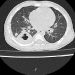

Ngày 13.8, bệnh nhân nhập viện tại Khoa C4 Gan mật, được chụp CT – scan phổi, có hình ảnh viêm phổi và được chuyển sang Khoa Hô hấp ngày 15.8.